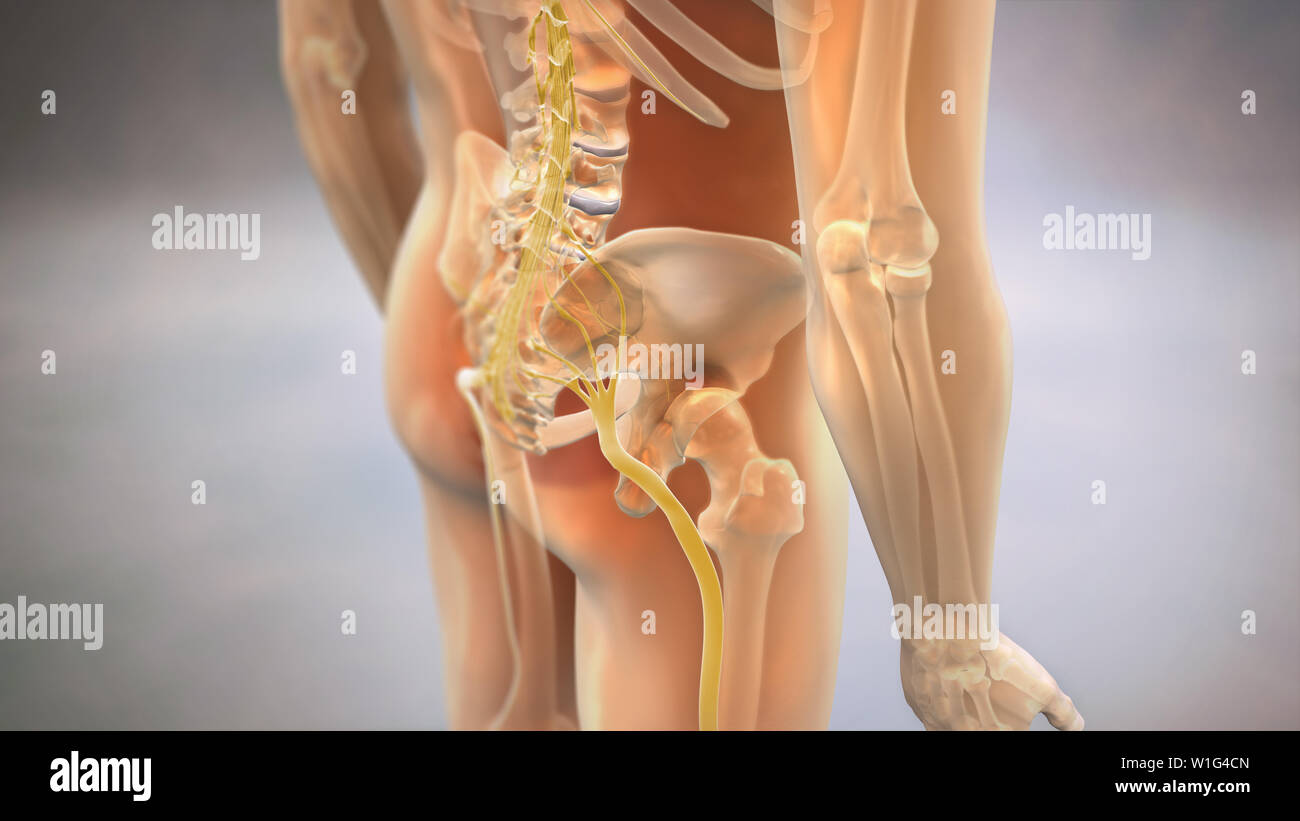

Douleur du nerf sciatique, illustration Banque D'Imageshttps://www.alamyimages.fr/image-license-details/?v=1https://www.alamyimages.fr/douleur-du-nerf-sciatique-illustration-image353192503.html

Douleur du nerf sciatique, illustration Banque D'Imageshttps://www.alamyimages.fr/image-license-details/?v=1https://www.alamyimages.fr/douleur-du-nerf-sciatique-illustration-image353192503.htmlRM2BEH8HY–Douleur du nerf sciatique, illustration

Nerf sciatique humain pincé, vision anatomique. illustration 3d. Banque D'Imageshttps://www.alamyimages.fr/image-license-details/?v=1https://www.alamyimages.fr/nerf-sciatique-humain-pince-vision-anatomique-illustration-3d-image364068055.html

Nerf sciatique humain pincé, vision anatomique. illustration 3d. Banque D'Imageshttps://www.alamyimages.fr/image-license-details/?v=1https://www.alamyimages.fr/nerf-sciatique-humain-pince-vision-anatomique-illustration-3d-image364068055.htmlRF2C48MEF–Nerf sciatique humain pincé, vision anatomique. illustration 3d.

Nerf sciatique humain pincé, vision anatomique. illustration 3d. Banque D'Imageshttps://www.alamyimages.fr/image-license-details/?v=1https://www.alamyimages.fr/nerf-sciatique-humain-pince-vision-anatomique-illustration-3d-image364067992.html

Nerf sciatique humain pincé, vision anatomique. illustration 3d. Banque D'Imageshttps://www.alamyimages.fr/image-license-details/?v=1https://www.alamyimages.fr/nerf-sciatique-humain-pince-vision-anatomique-illustration-3d-image364067992.htmlRF2C48MC8–Nerf sciatique humain pincé, vision anatomique. illustration 3d.